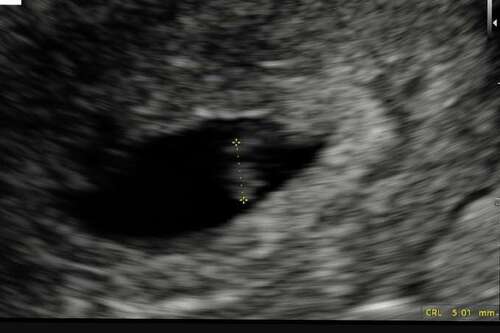

Geen ovulatietesten gedaan maar wel ongeveer gevoeld, dus niet zeker maar 3 ...

Tenzij je een hele late eisprong en innesteling hebt gehad.

In mijn ogen is dit een mooie vooruitgang. Oké je bent minder ver maar je b ...

Ja is ook zo! Maar het maakt me onzeker omdat ik vrij vaak vaste cyclus heb in de maand.

Nu was ik 1 dag erg ziek en koorts en moe. En die dag was ik erg licht bijna niet zichtbaar de test en dat was 2 dagen voor nod gebaseerd op cyclus dagen 28